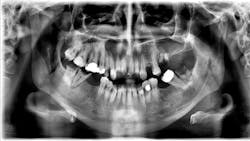

A healthy 37-year-old male presents with pain on the lower-left and lower-right sides of his mouth. He states that he drinks a lot of soda, and he knows his teeth are bad. He feels like the area is swelling, and the associated pain is keeping him from sleeping.

A limited exam reveals rampant decay. The panoramic radiograph shows badly decayed teeth on the lower right side, with an apical radiolucency and associated swelling in the buccal vestibule. Also noted is a well-defined radiolucency above the apexes of tooth nos. 5–9. There is some expansion around the bone; the lesion is not fluctuant or mobile. Nos. 5–9 are severely decayed.